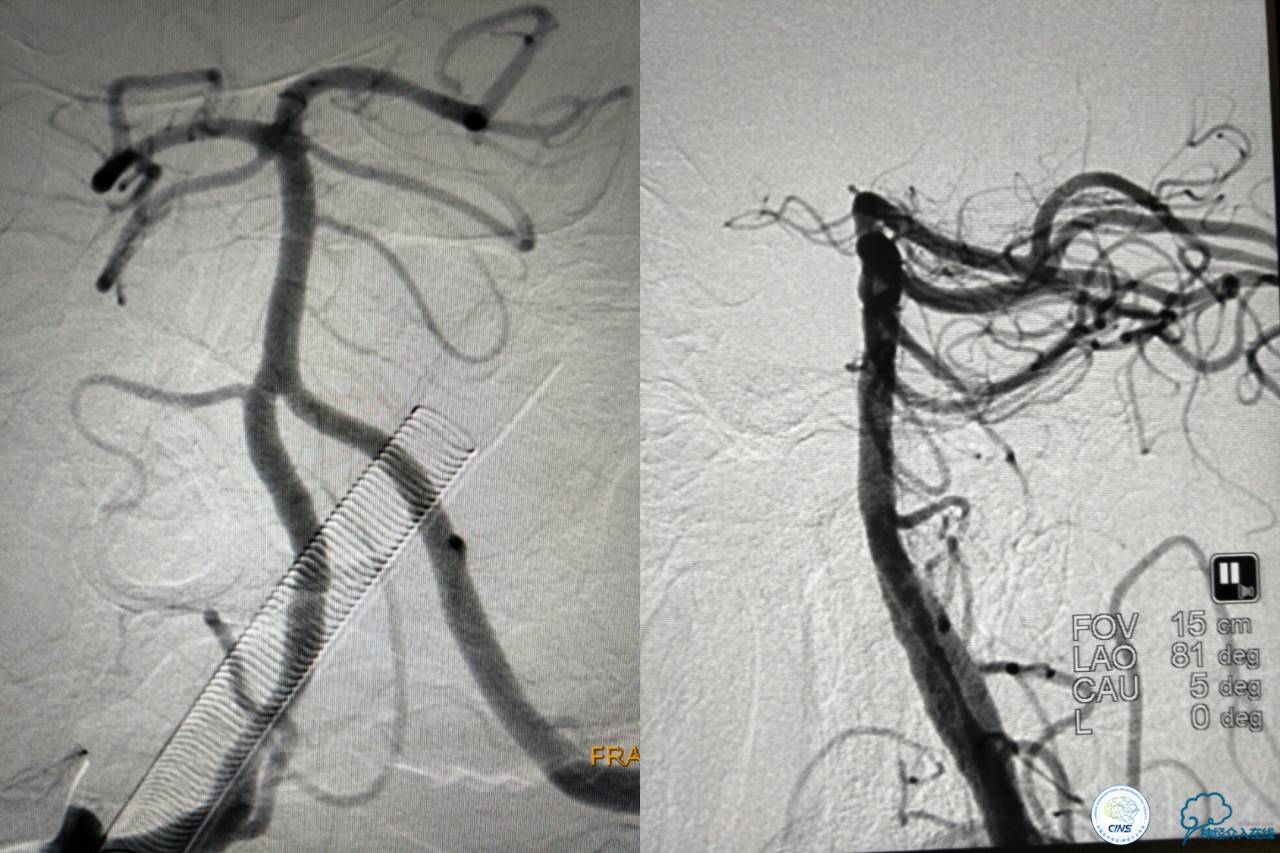

好大的血栓,支架释放后,血管无复流,拉一把!

没错,没看错!血管成功实现再通,术中取栓的栓子如下。

术后生命体征平稳,成功撤呼吸机,肌力较前好转,复查头颅CT:

右侧丘脑高密度影,右侧枕叶可能也有梗死,祈祷慢慢恢复吧!